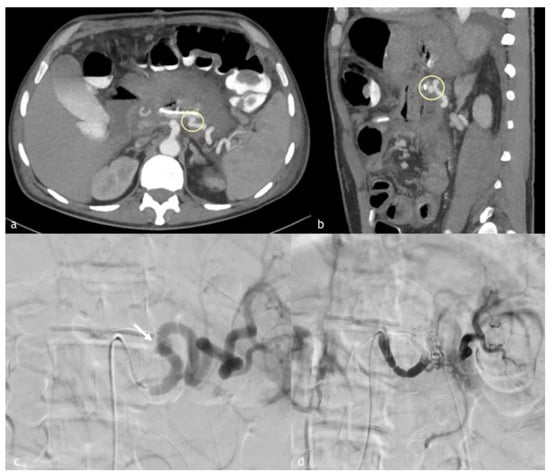

Figure 4. (ad). A 55-year-old man presented to our emergency department for acute abdominal pain. (a,b) Axial MIP reconstruction images demonstrate celiac trunk dissection with multiple beading or webs, aspects of the splenic artery suggestive of SAM. (c) Digital subtraction angiographic image that shows multiple beading and webs of the splenic artery vessel wall. (d) Post-embolization angiographic control, after very proximal embolization for impossibility to more distal catheterization, demonstrating distal recanalization of splenic artery by gastroduodenal artery.